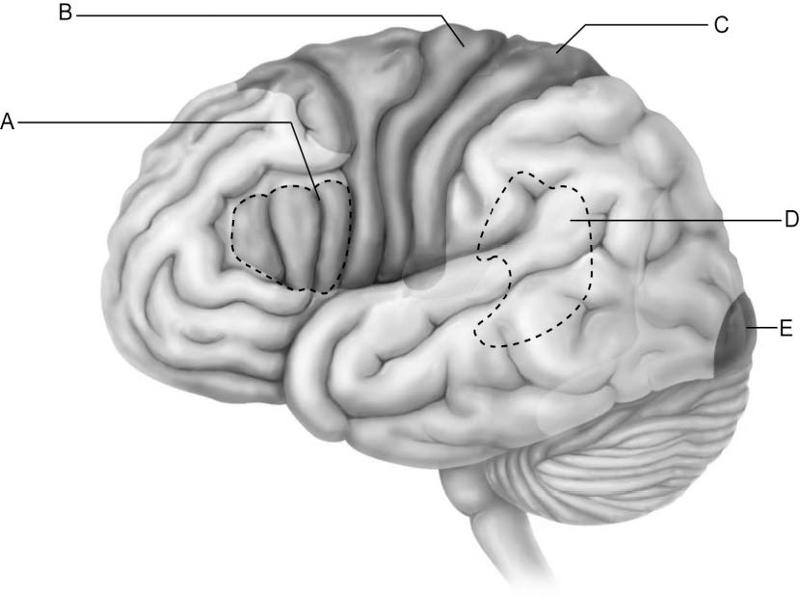

Which letter indicates the primary visual cortex, which receives

information from neurons in

the retina of the eye?

A)

A

B) B

C) C

D) D

E) E

E

Which letter indicates Broca's area, which controls the motor

movements necessary for

speaking?

A) A

B) B

C)

C

D) D

E) E

A

Which letter indicates Wernicke's area, which is important for

understanding spoken words?

A) A

B) B

C) C

D)

D

E) E

D

Which letter indicates an area that is characterized by huge neurons

known as pyramidal cells?

A) A

B) B

C) C

D)

D

E) E

B

Which letter indicates the primary somatosensory cortex?

A)

A

B) B

C) C

D) D

E) E

C